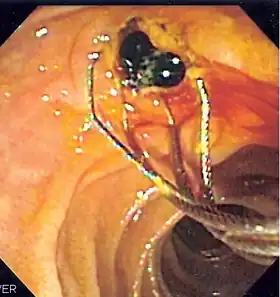

![]() Duodenoscopic image of two black pigment stones extracted from common bile duct after sphincterotomy | |

When needed, the sphincters of the ampulla and bile ducts can be enlarged by a cut (sphincterotomy) with an electrified wire called a sphincterotome for access into either so that gallstones may be removed or other therapy performed.[10]

Other procedures associated with ERCP include the trawling of the common bile duct with a basket or balloon to remove gallstones and the insertion of a plastic stent to assist the drainage of bile.[11] Also, the pancreatic duct can be cannulated and stents be inserted.